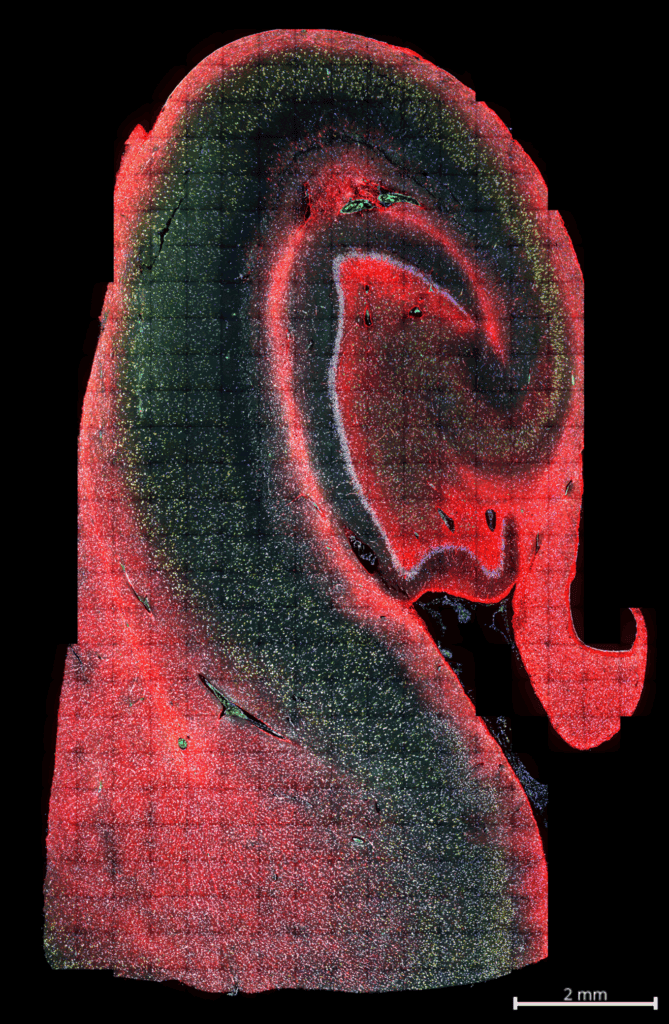

Whole transcriptome spatial data from hippocampus tissue. The immunofluorescence image below shows histone in blue, AF in green, rRNA in yellow, GFAP in red, DAPI in gray. An H&E image is also available for comparison.